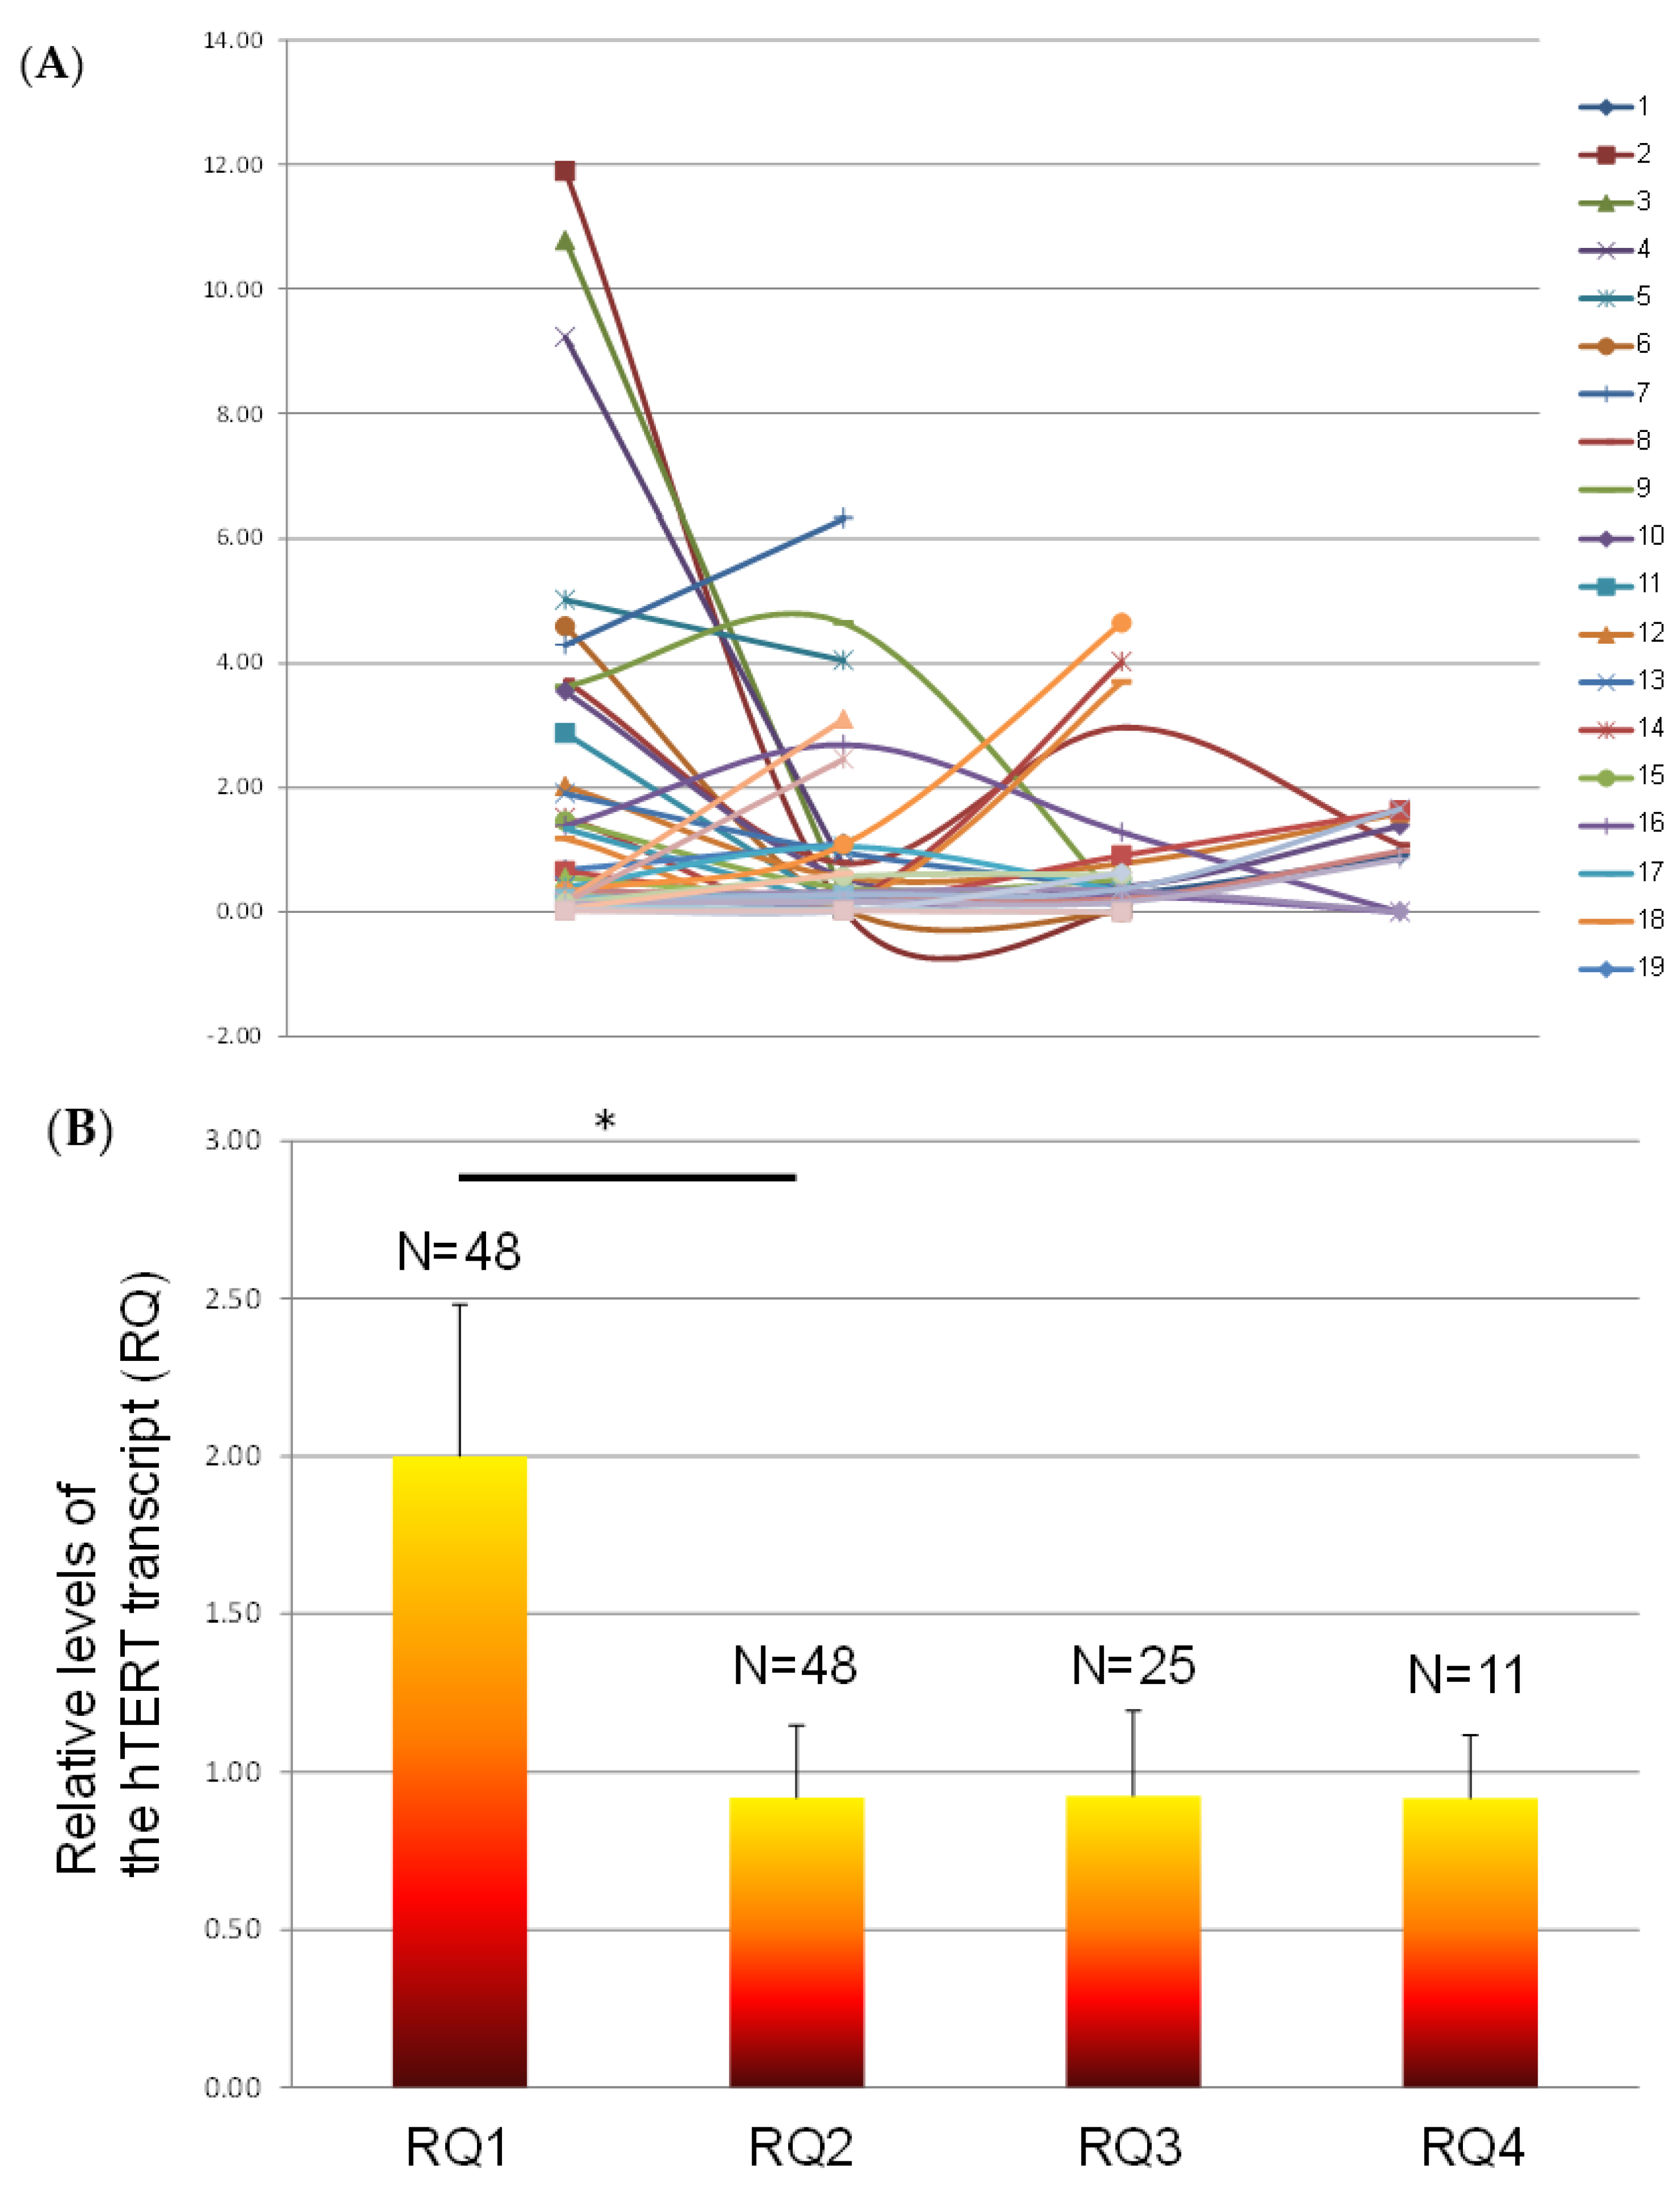

3.4. The Levels of Exosomal hTERT Transcript throughout Follow-Up of the Disease